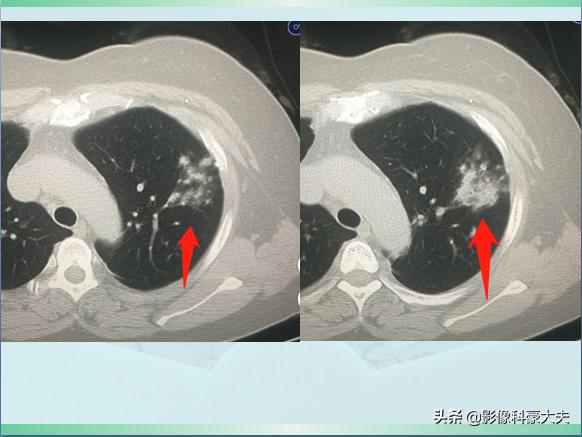

星星点点的小斑片影

上图是一位54岁女病人,因为发烧、咳嗽3天做肺部CT,发现左上肺斑片状影,密度不均,边界不清,提示肺炎。

使用抗生素治疗4天后复查,病灶密度增加,同时内部出现了几个小空洞:

融合实变,可见空洞